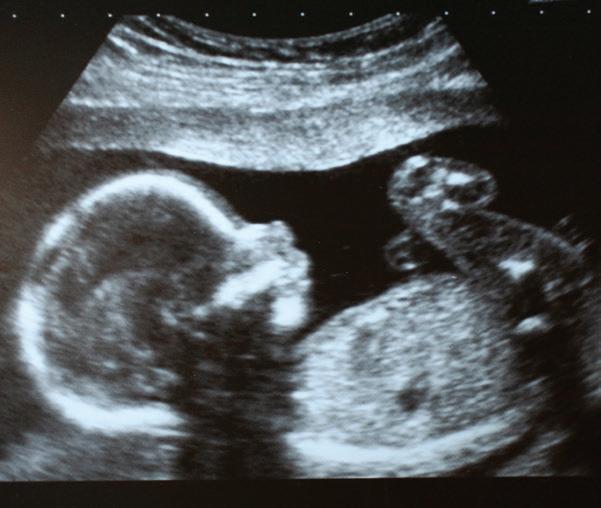

A week went by with no word from Charlotte. Her PDL coach decided to reach out to her and see how her ultrasound appointment went at the pregnancy center. The coach was flooded with such joy when she found out that Charlotte decided to keep her baby after her ultrasound. When Charlotte saw God’s precious creation on the screen, she said there was no other choice but to choose life.

When our hotline coaches can reassure callers that they are not alone, and then refer them to a pregnancy center where they can see an ultrasound of the life they are carrying inside of them, lives are saved.

Tiffany visits the pregnancy center (freestanding or church-based), which provides an ultrasound, info about her options, parenting education, and also serves Jeff, the father of her unborn baby. They hear the Gospel and choose life together!

I connected her to a local pregnancy center where she met her precious baby on the ultrasound and chose life. We also connected her to a church, as well as a ministry that focuses on mentoring first time moms.

• Ultrasound Scans